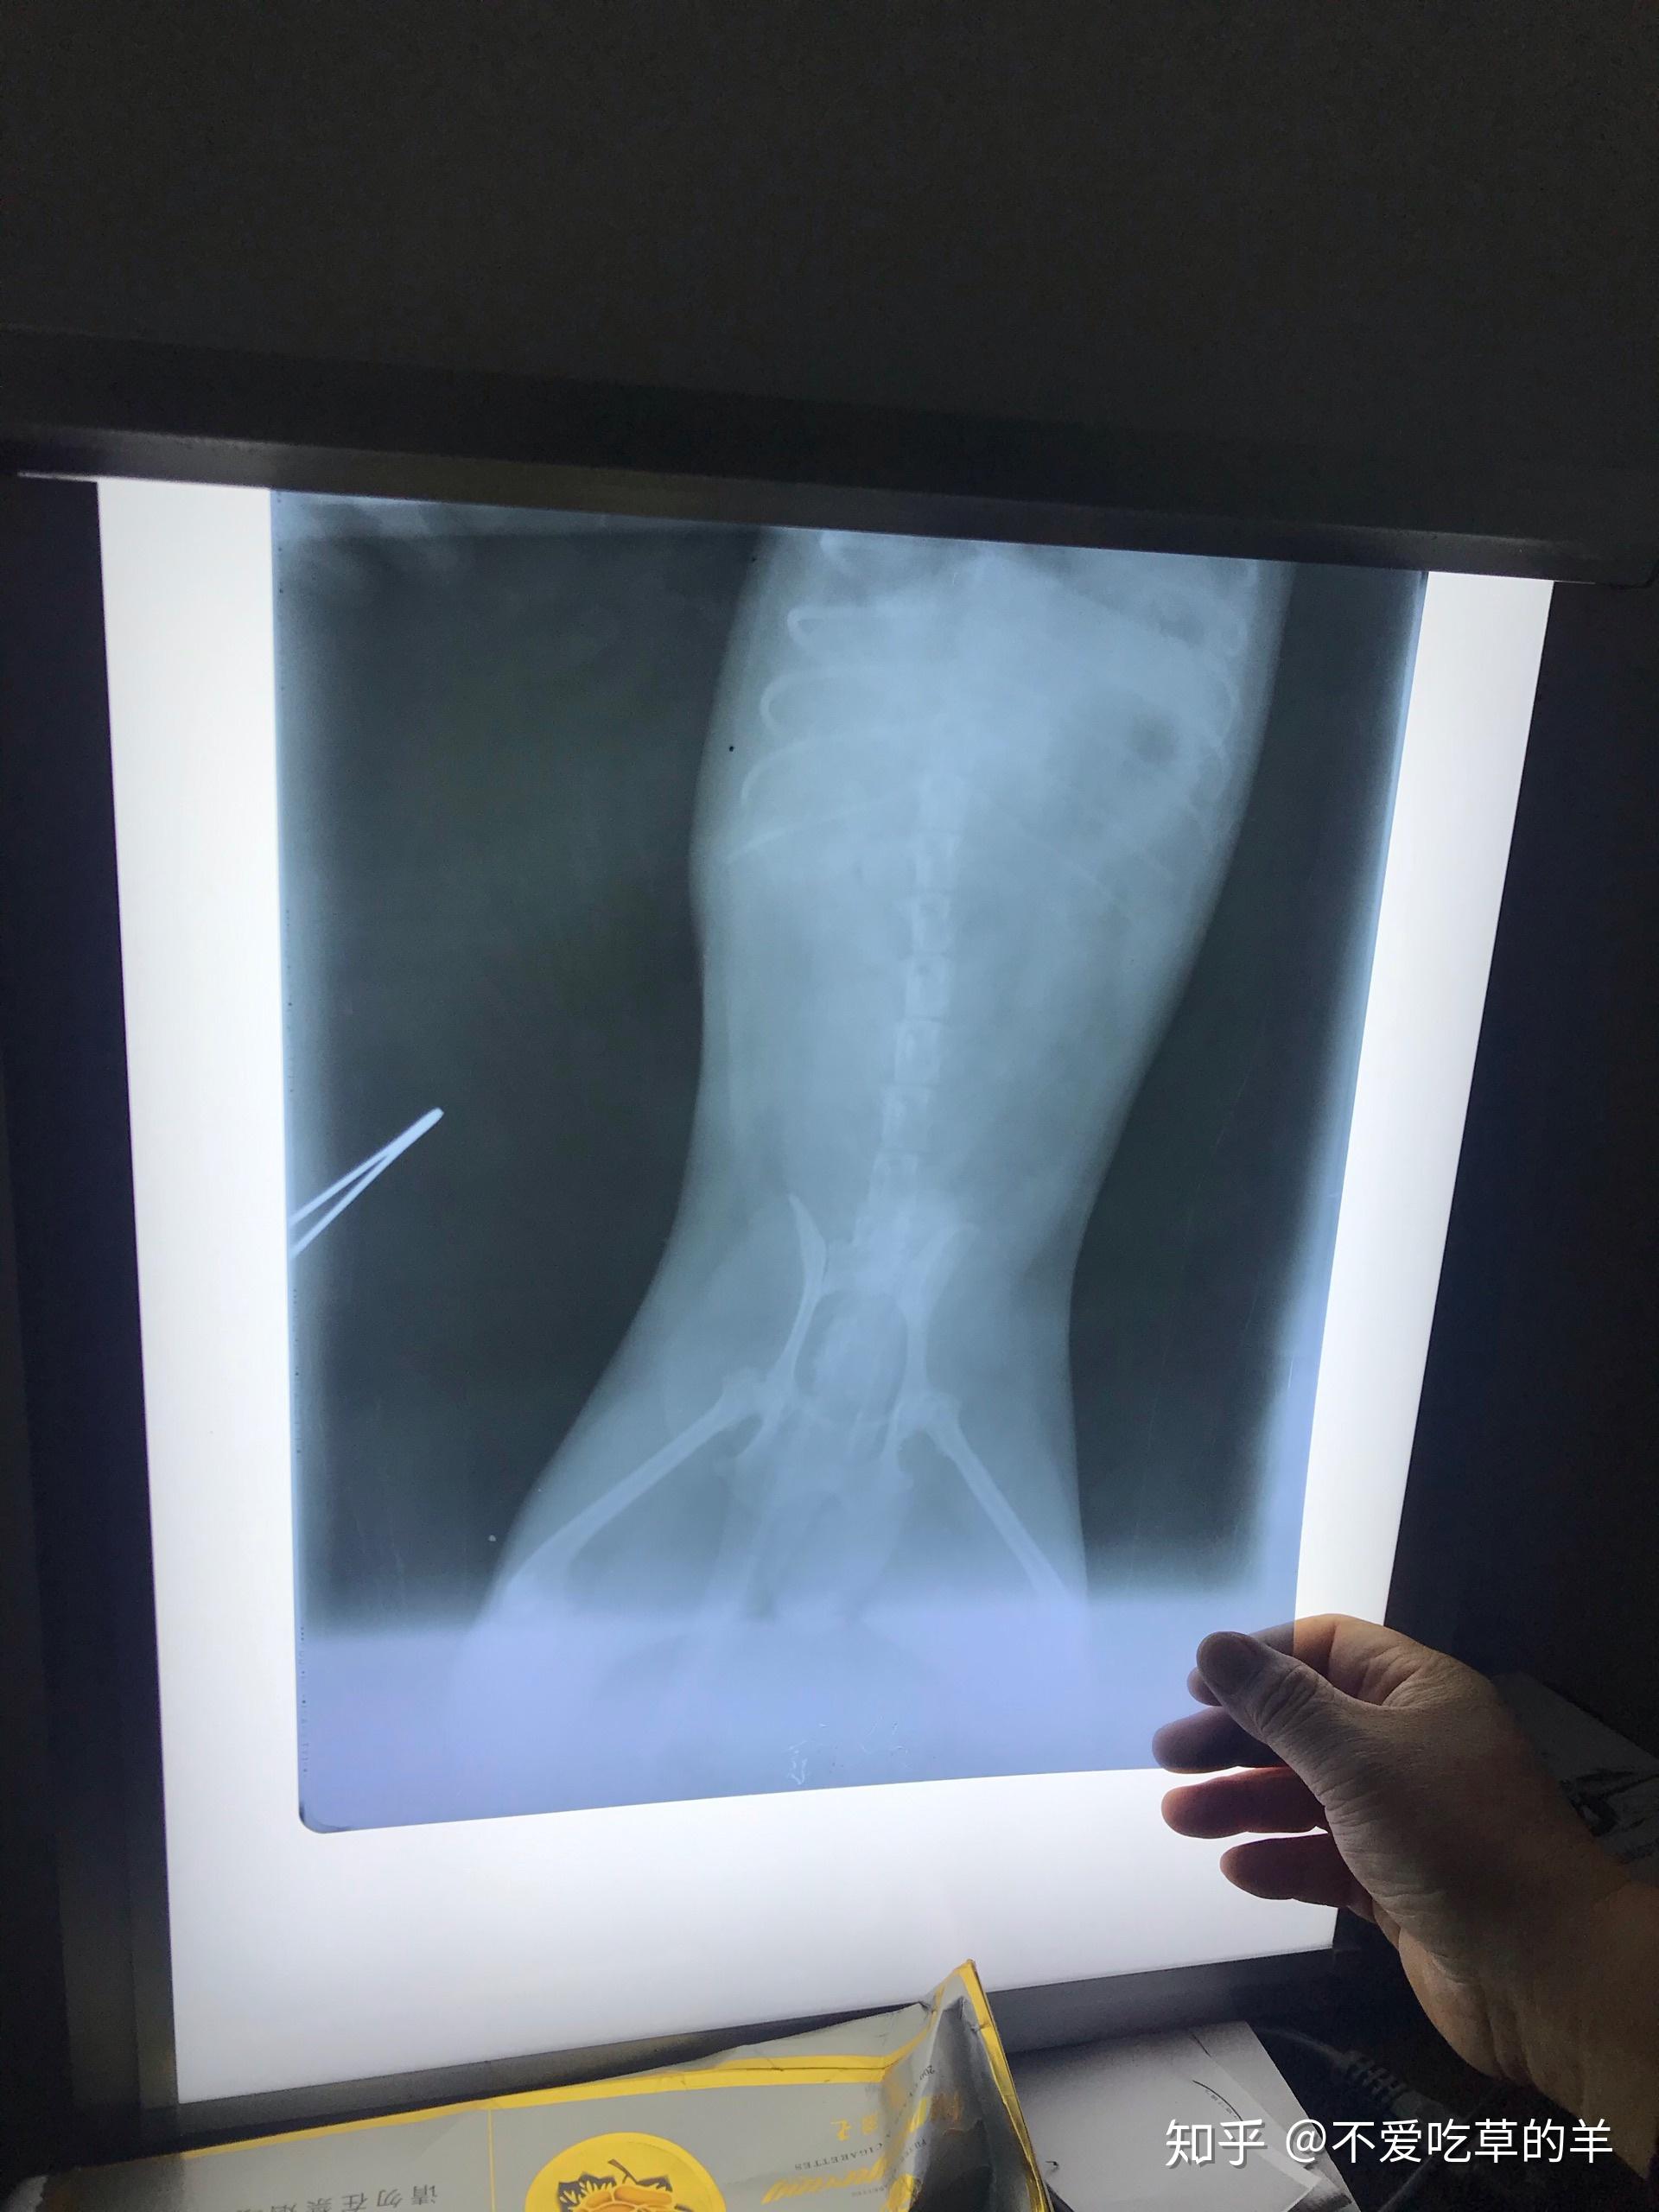

狗狗吃了老鼠药诱发胰腺炎命悬一线.